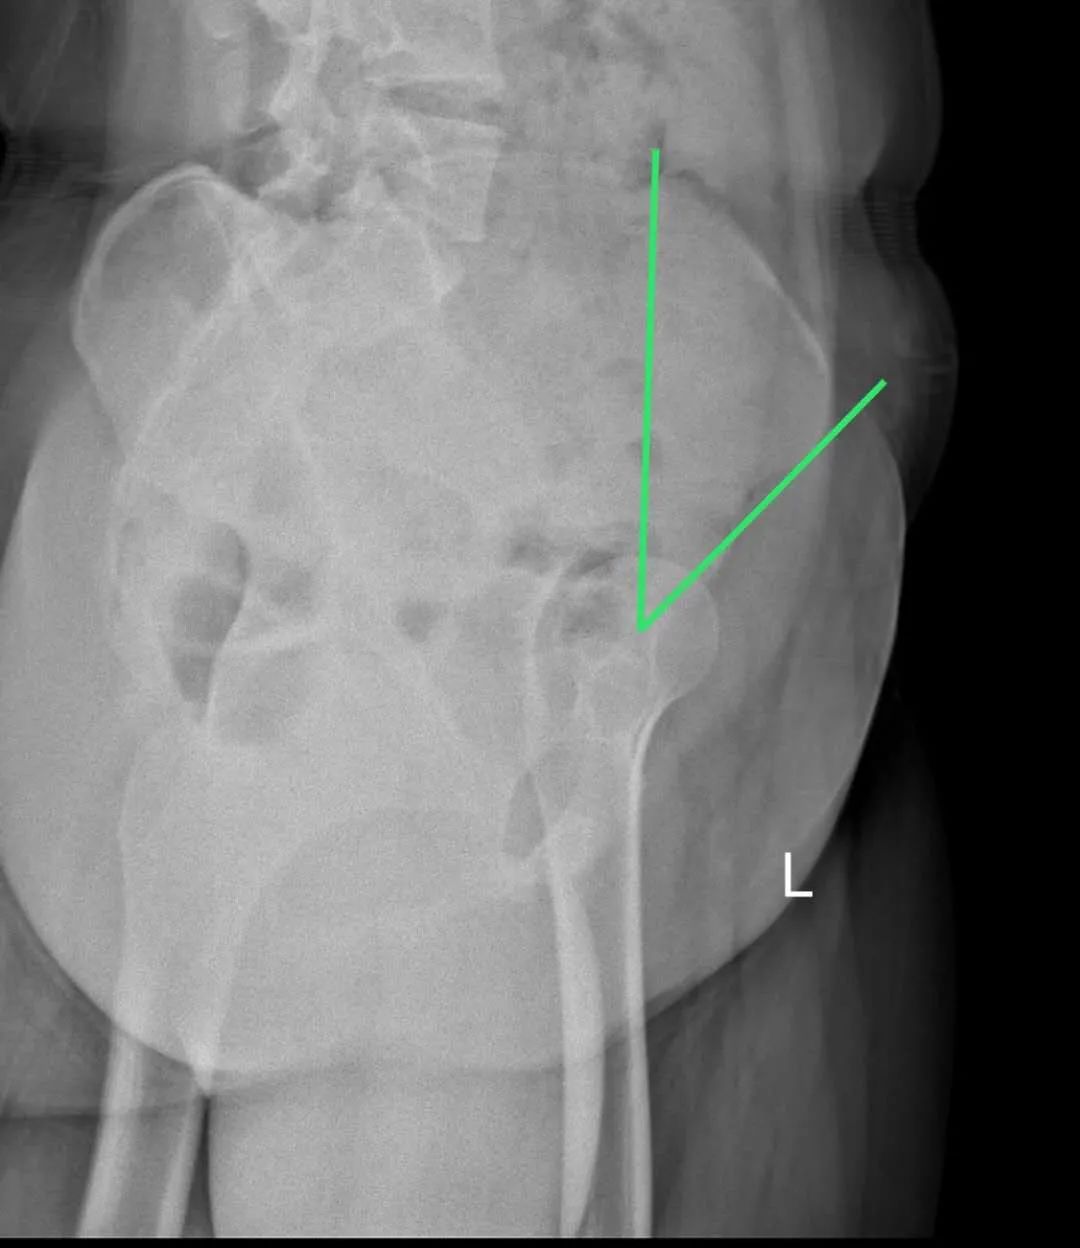

今年15歲的孫某,出現(xiàn)雙側(cè)髖部疼痛,呈持續(xù)性隱痛,只采取口服藥物的保守治療,但是疼痛未見減輕反而愈演愈烈,于是到誠德骨科醫(yī)院集團(tuán)(市中院區(qū))尋求專家的幫助,經(jīng)過多方檢查和論證后,劉德俊院長診斷為:

先天性多發(fā)性骨骺發(fā)育不良,并決定為其實(shí)施“髖臼周圍截骨術(shù)”。

術(shù)后